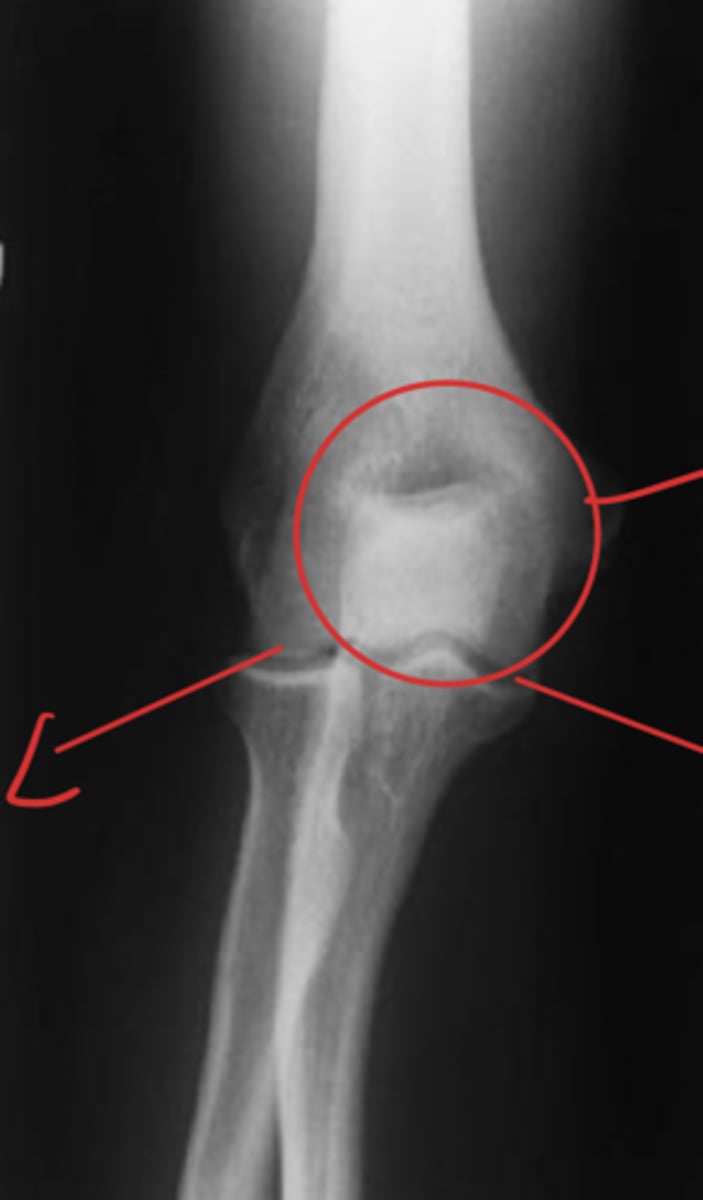

Medial epicondyle avulsion fracture

What is the issue?

AP internal oblique elbow

What view is this?